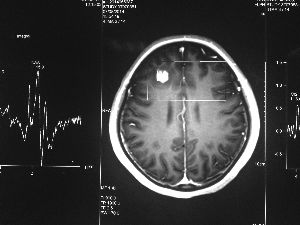

今年6月份,張敏在宿舍休息時,又發(fā)起了癲癇,也是口吐白沫,渾身抽搐。送到蘇州一家大醫(yī)院,頭顱核磁共振檢查出,張敏大腦右額葉處有一處病灶,也就是大腦額頭處有個東西。

腦袋里的東西,到底是腫瘤還是其他什么東西,這個謎像個石頭一樣,壓得張敏一家人喘不過氣。7月份,張敏一家又來到南京腦科醫(yī)院求醫(yī),第三次檢查后,醫(yī)生覺得很像是寄生蟲。不過,影像的檢查,只能作為醫(yī)生推測的依據(jù),具體是什么,只有手術(shù)拿出來后才能知道。